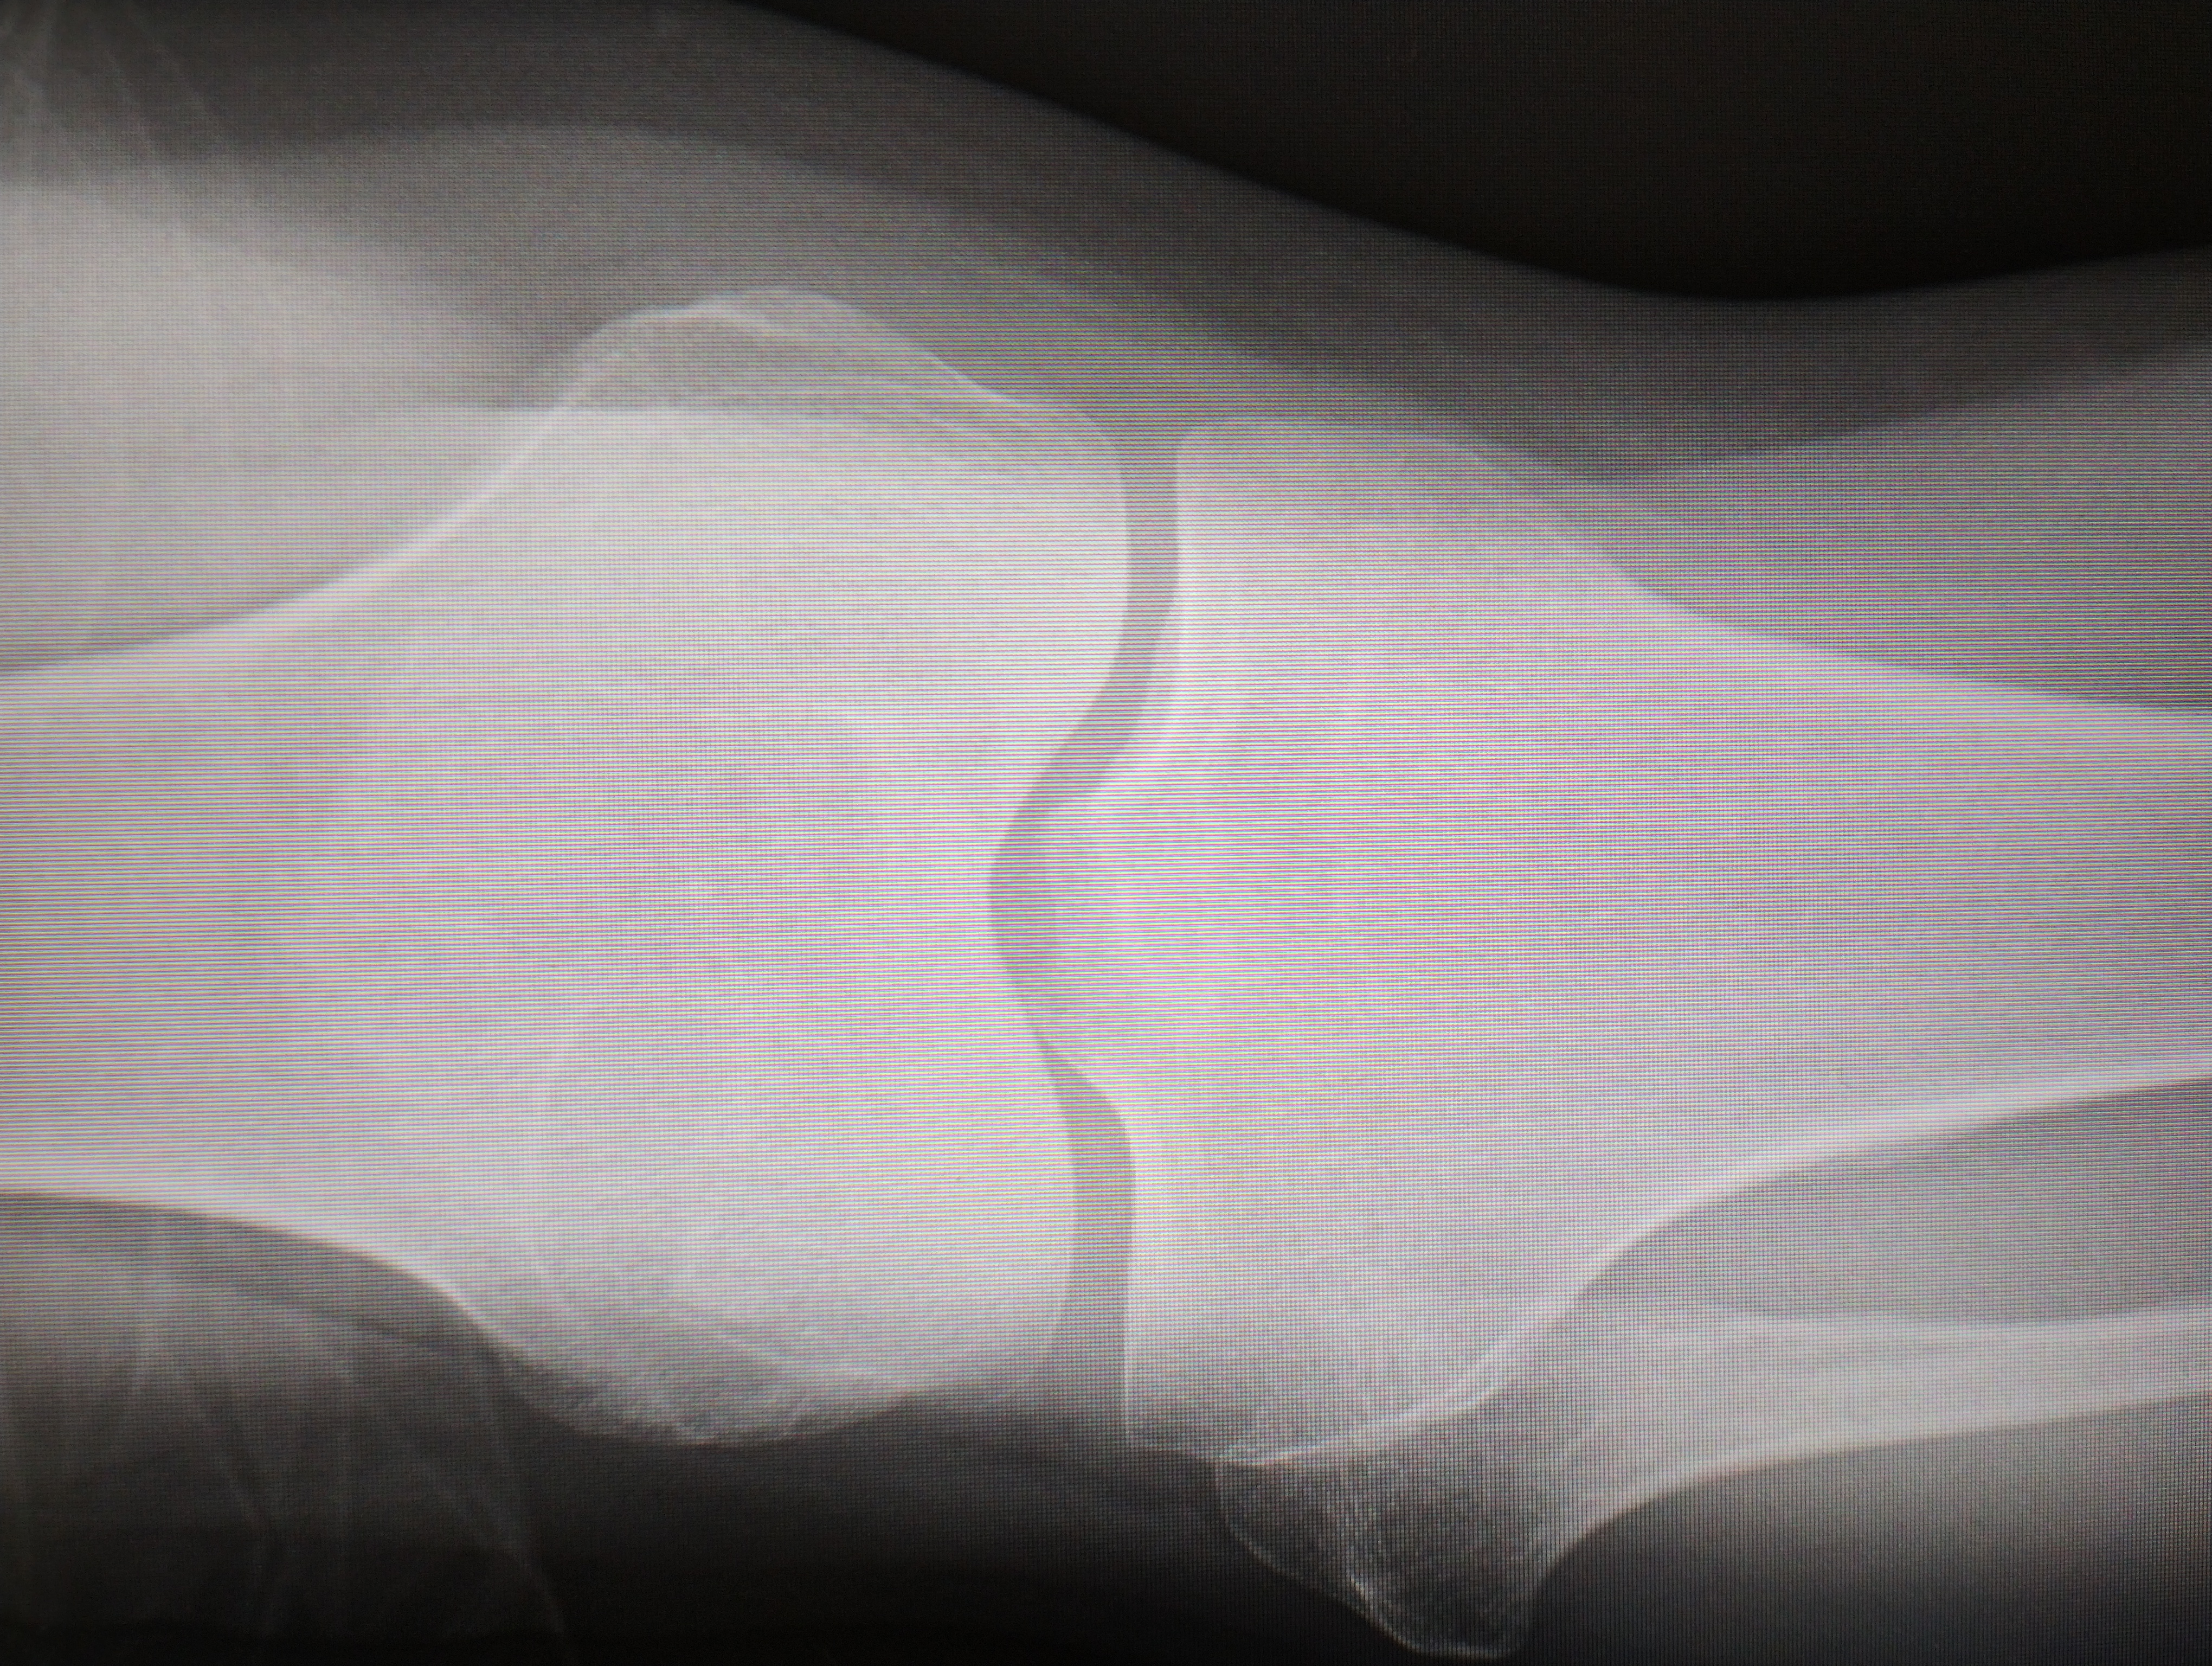

筋でも痛めたのかなぁと思いつつ近くの整形外科にいってみてレントゲンを撮ってもらいました。

X線では分からなかったのですが、MRIだと判明致しました。

ではなく、「右脛骨骨挫傷」とのこと。

骨折一歩手前でそのまま歩き続けたら陥没骨折の可能性ありとのこと、∑(;谷)エエエエエエエエエエエエエエエ・・・